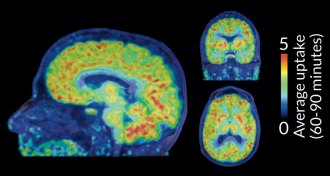

Scientists get a glimpse of chemical tagging in live brains

For the first time scientists can see where molecular tags known as epigenetic marks are placed in the brain.